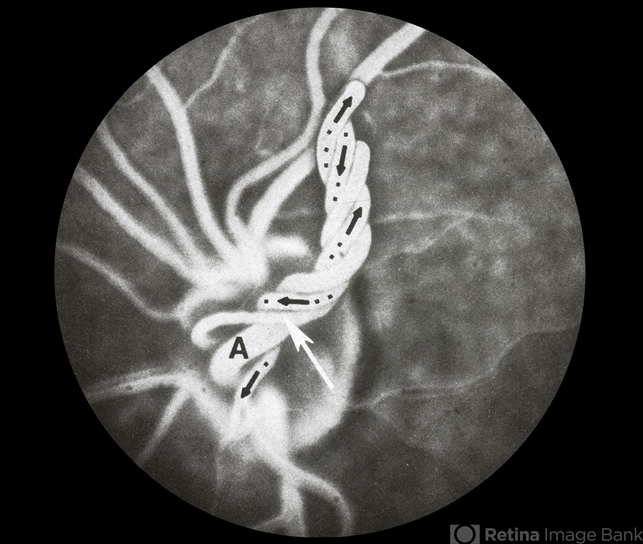

- prepapillary vascular loop

- No history or color photo. Flurescein angiogram.